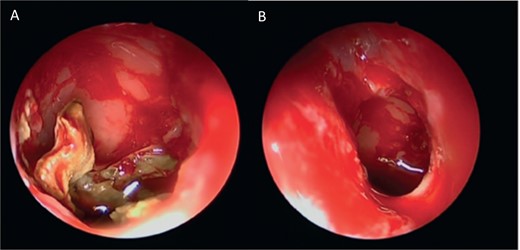

Intra-operative endoscopic maxillary examination (A and B) showing invasive fungal debris.

A 12-year-old young girl with relapsing acute myeloid leukemia presented with fever, headache, and left maxillary facial pain. Her symptoms were associated with blood-tinged nasal discharge. Nasal endoscopic examination showed friable ulcerative mucosa of the left middle turbinate and osteo-meatal complex which raised a clinical suspicion of invasive fungal sinusitis. Thus, a contrast-enhanced CT scan (CECT) (Fig. 3) was necessary which showed enhancing left maxillary sinus opacity suggestive of acute invasive fungal sinusitis. The patient underwent urgent endoscopic medial maxillectomy with removal of invasive fungal debris (Fig. 4) along with debridement of left middle turbinate, medial maxillary wall, and orbital floor. A diagnosis of invasive mucormycosis was confirmed by histopathology. The patient was started on aggressive treatment in the form of intravenous and oral antifungal medications. She was regularly followed up for the next 5 years with no evidence of recurrence.